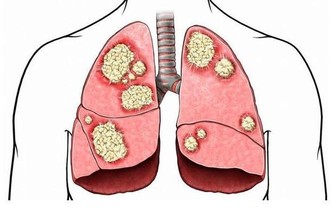

4、肺部有毒:合谷穴

肺部有毒的體現之一即是呈現便秘景象。

可用拇指和食指捏住合谷穴,用力按壓。